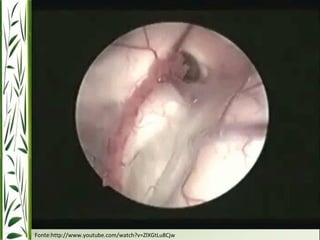

Terceiroventriculostomia

http://www.youtube.com/watch?v=w_-EfoCyJFU

Fonte:http://www.youtube.com/watch?v=ZlXGtLu8Cjw